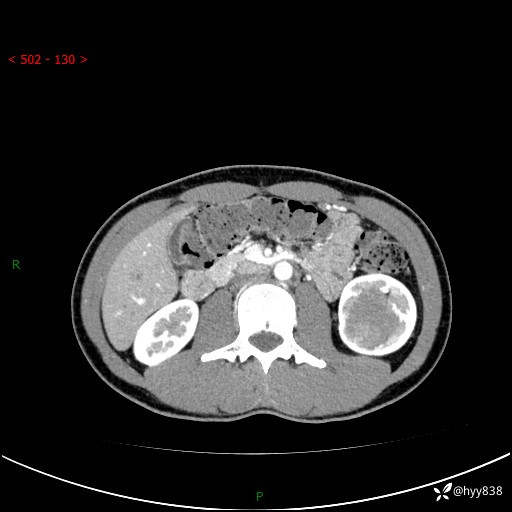

现病史:患者昨日中午进食后出现明显腹痛,腹泻,在我院急诊科行补液及对症治疗,双肾输尿管彩超提示左肾占位(5.2*4.3cm),平素无明显腰痛,无再发肉眼血尿等情况,现为求处理左肾占位,遂来我院,门诊以左肾占位收治入院。 患者起病以来,精神、食欲、睡眠尚可,大便可,小便如上,体力体重无明显下降。

双肾CT平扫+增强(三期)